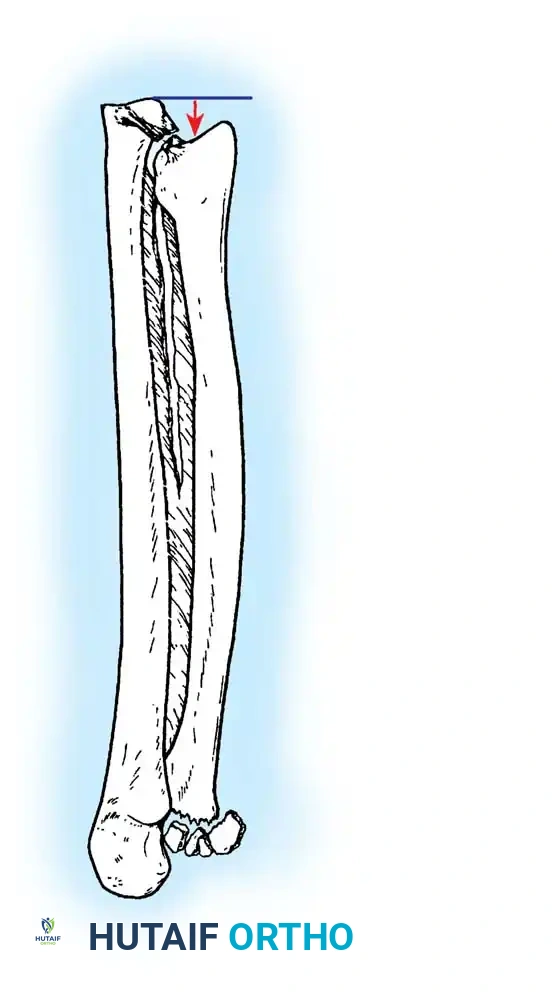

The primary goal of surgical intervention in the forearm and elbow is the exact restoration of anatomical alignment, axial length, and rotational stability. In the proximal ulna, the olecranon forms the greater sigmoid notch, articulating with the trochlea of the humerus. Any disruption here not only compromises the extensor mechanism but also threatens the intrinsic stability of the elbow joint.

FRACTURES OF THE OLECRANON

In adults, displaced fractures of the olecranon necessitate open reduction and internal fixation (ORIF). Because the olecranon is an intra-articular structure, reduction must be anatomically exact. Any residual irregularity or step-off of the articular surface inevitably leads to limited motion, delayed functional recovery, and early-onset post-traumatic osteoarthritis.

The chosen fixation construct must be biomechanically robust enough to withstand the powerful tensile forces of the triceps brachii. Rigid fixation allows for the initiation of gentle, active range-of-motion (ROM) exercises well before radiographic evidence of complete osseous union is visible.

The tension band principle is applicable to fractures of the olecranon that are non-comminuted and located well proximal to the coronoid process. It is most commonly used for transverse avulsion fractures.

Biomechanics of the Tension Band:

The superficial (posterior) surface of the olecranon is the tension side of the bone. A figure-of-eight wire placed on this surface converts the tensile forces generated by the triceps into compressive forces across the articular fracture line, utilizing the humeral trochlea as a fulcrum.

Surgical Warning: A simple wire loop is biomechanically inferior to a figure-of-eight loop. If a simple loop is used—especially if its axis lies anterior to the mid-axis of the olecranon—the pull of the triceps will cause the fragments to separate posteriorly, leading to articular step-off and limited extension.

Fig. 54-53 A and B, Simple loop is not as satisfactory as figure-of-eight loop for fixing fracture of olecranon. C, Simple loop is insufficient when its long axis is in or anterior to long axis of olecranon.